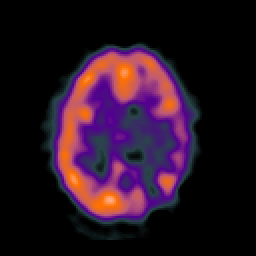

SPECT TC Study #6 -- Slice #34

[Home][Help][Clinical][Tour 1][Tour 2][Tour 3] Slice 34